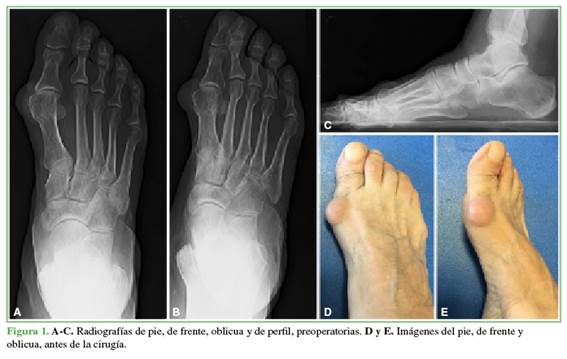

A todos los pacientes se les tomaron radiografías anteroposterior, latero-lateral con apoyo y oblicua de pie antes de la cirugía (Figura 1), en el posoperatorio (Figura 2) y a los 18 meses de la intervención (Figura 3) para establecer el ángulo intermetatarsiano (IM), el ángulo del hallux valgus (HV), el ángulo articular metatarsiano distal (AMD), la congruencia de la articulación metatarsofalángica, el ángulo interfalángico, la altura del M1, el grado de deformidad, el grado de lesión, la movilidad articular del hallux, la presencia de dolor, y para planificar la cirugía.

Se llevó a cabo un estudio prospectivo observacional. Entre agosto de 2015 y enero de 2019, se trató a 21 pacientes (23 pies) con hallux valgus asociado a hallux rigidus grado 2, según la clasificación de Coughlin y Shurnas.8 Esta clasificación los divide en cinco grados (de 0 a 4), considera el rango de movilidad de la articulación metatarsofalángica del hallux, los cambios radiográficos y las manifestaciones clínicas (Tabla 1). El estadio 2 de la clasificación corresponde a una flexión dorsal de 10-30° o una pérdida del 50-75% de la movilidad comparada con la del lado sano. En las radiografías, se observan osteofitos dorsales, laterales y mediales, cabeza de aspecto aplanado, menos del 25% de compromiso de la región dorsal del espacio articular, estrechamiento y esclerosis del espacio articular de leve a moderada, sin compromiso de los sesamoideos. Con respecto a la clínica, el paciente siente dolor de moderado a intenso y hay rigidez que puede ser constante.

El método se seleccionó luego de un análisis y una evaluación radiográfica.